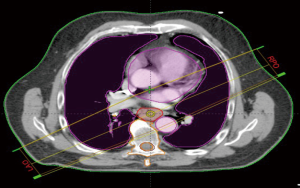

We retrospectively contoured the thoracic vertebral bodies of eligible patients. For proximally located tumors (n=7), two vertebral levels above the superior aspect of the planning treatment volume (PTV) were included in the vertebral volume in addition to thoracic vertebral volumes. Based on our population and contouring approach all vertebral volumes contoured were limited to C5 or below. Dose volume histograms (DVH) were evaluated to record the absolute vertebral volume (VVert), in ccs, receiving between 10–40 Gy as well as the mean vertebral dose. We evaluated the splenic volume dosimetric (SV) parameters (in ccs) from volumes between 5–30 Gy along with the mean dose. We also sought to evaluate the effect of radiotherapy dose to the systemic circulating lymphocyte pool by collecting mean body dose (MBD). During collection of MBD we noted the total length of CT simulation scans (and hence relative volume of body captured) was not uniform across all patients due to the retrospective nature of our analysis. In an effort to account for dose to peripheral lymphocytes in a more standardized manner, we performed dosimetric analysis on a volume designed to account for the radiotherapy dose received to the majority of the thoracic blood pool. We termed this volume “standardized thoracic volume (sTV)” and it includes a boolean sum of the contours of the heart to the superior portion of the aortic arch, the entire aortic arch volume, and the entire lungs, while excluding thoracic vertebrae. Mean dose to sTV was calculated and designated by the term mean dose (sTV is displayed in Figure 1). We hypothesized that this volume would capture a majority of cardiac output during daily RT delivery and had the advantage of excluding thoracic vertebral volumes. Radiation was delivered using Intensity modulated therapy (IMRT) or 3-dimensional conformal therapy (3-DCRT). Standard dose constraints to the OARs in the thorax such as those used in RTOG 0436 were followed on all plans (25).